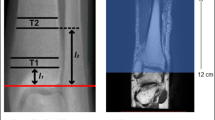

Perfusion MRI measures tissue hemodynamics, and perfusion MRI studies in bone marrow have been primarily performed using dynamic contrast-enhanced (DCE) MRI. T1-weighted MR images are acquired before, during, and after rapid intravenous injection of Gd-based contrast agents that shorten T1 when the bolus passes through the tissue. Perfusion parameters, including maximum enhancement, slope, and transit time, can be extracted from the perfusion time-signal curve, using empirical quantitative methods. To obtain more machine-independent parameters that are physiologically meaningful, including blood volume, flow, transit time constants, and permeability, tracer kinetic modeling has been applied with the requirement of an arterial input function (AIF). In femur, CVs of MR perfusion (scan and rescan at 1 week) ranged from 0.59 (enhancement slope femoral head) to 0.98 (enhancement maximum acetabulum) (51). Decreased perfusion was observed with decreased BMD in vertebral body (45, 59, 60) and in femur (61, 62). Furthermore, femur perfusion parameters (and marrow fat) at baseline predicted bone loss in femoral neck over 4 years (63). However, the effect of fat signal on perfusion parameter quantification needs to be addressed (64•, 65). Despite interesting results, the usage of contrast agent has impeded wide applications of perfusion MRI for studying osteoporosis.

Diffusion MRI is sensitive to Brownian motion, or “self-diffusion” of water molecule that is related to tissue microstructure and organization by using an additional pair of diffusion-weighting or dephasing gradient pulses into existing pulse sequences. Diffusion MRI based on single-shot echo-planar imaging (ssEPI) is the most commonly used sequences due to its fast acquisition and robustness to motion. However, applying ssEPI-diffusion MRI in bone marrow is challenging due to the susceptibility difference between bone and marrow and the images are prone to geometric distortions especially at high resolution. Methods to reduce such distortions include using reduced-FOV EPI, single-shot turbo-spin-echo or fast-spin-echo, and steady-state free-precession sequences showed promising results in bone marrow applications (58). Apparent diffusion coefficients (ADCs) of normal vertebral bone marrow were reported to range between 0.2 and 0.6 × 10−3 mm2/s, which is lower than almost all other tissues except fat in human body (58). The slow diffusion demands large diffusion weight which however will result in low SNR. Marrow ADC were reported to decrease from L1–L5 (66) and decrease with increasing age (67, 68), which may be explained by increased marrow fat from L1–L5 and with increasing age thus more restriction to the water diffusion. However, it should be noted that, because fat has very low diffusion, data acquisition without fat suppression or with less optimal fat suppression will result in underestimates of marrow ADC (65).